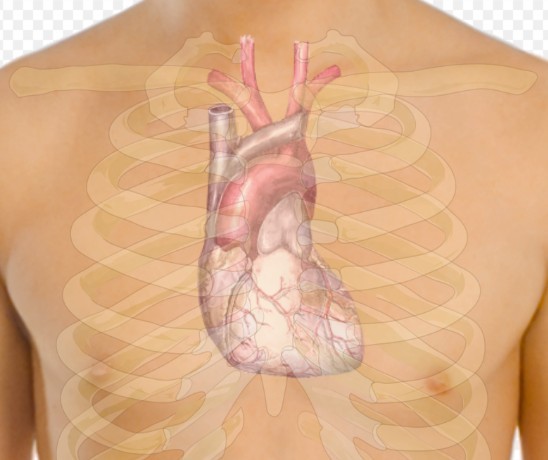

В первую очередь Мария Кириллова подчеркнула вред курения, отмечая, что оно повреждает сосуды, способствуя развитию атеросклероза, ишемической болезни сердца и артериальной гипертонии.

Другим фактором, влияющим отрицательно на сердце, является употребление алкоголя. Врач подчеркнула, что нет безопасной дозы алкоголя, и даже умеренное употребление может привести к повышению артериального давления и нарушению сердечного ритма.

Кириллова также выделила неправильный рацион питания как фактор, способствующий проблемам со здоровьем сердца. Особенно вредны фастфуд и продукты, содержащие насыщенные жиры и пальмовое масло, так как они повышают уровень холестерина и сахара в крови, что может привести к набору лишнего веса и увеличить риск инфаркта и инсульта, сообщает Вечерняя Москва.